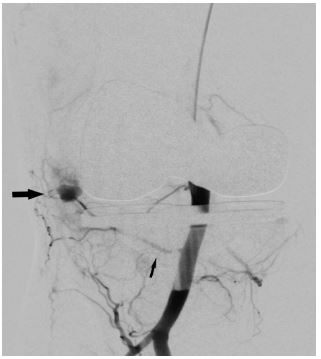

In view of continued knee joint swelling, the patient underwent right lower limb angiography the following week through the right femoral artery approach which identified a Pseudoaneurysm arising from the inferior medial genicular artery. This was embolized using 250 microns’ particles- embospheres and 2mm push able coils. Selective angiogram performed from superior medial and lateral genicular artery showed abnormal blush and pruning was done using 250-micron embospheres (Figures 3,4 & 5). An Ice pack was placed over the knee while instilling embolic agent particles to cause vasoconstriction of the skin arterial supply to avoid ischemia.

Figure 3: Angiography done through catheter in popliteal artery shows pseudoanuerysm (Solid arrow) arising from inferior medial geniculate artery (thin arrow).